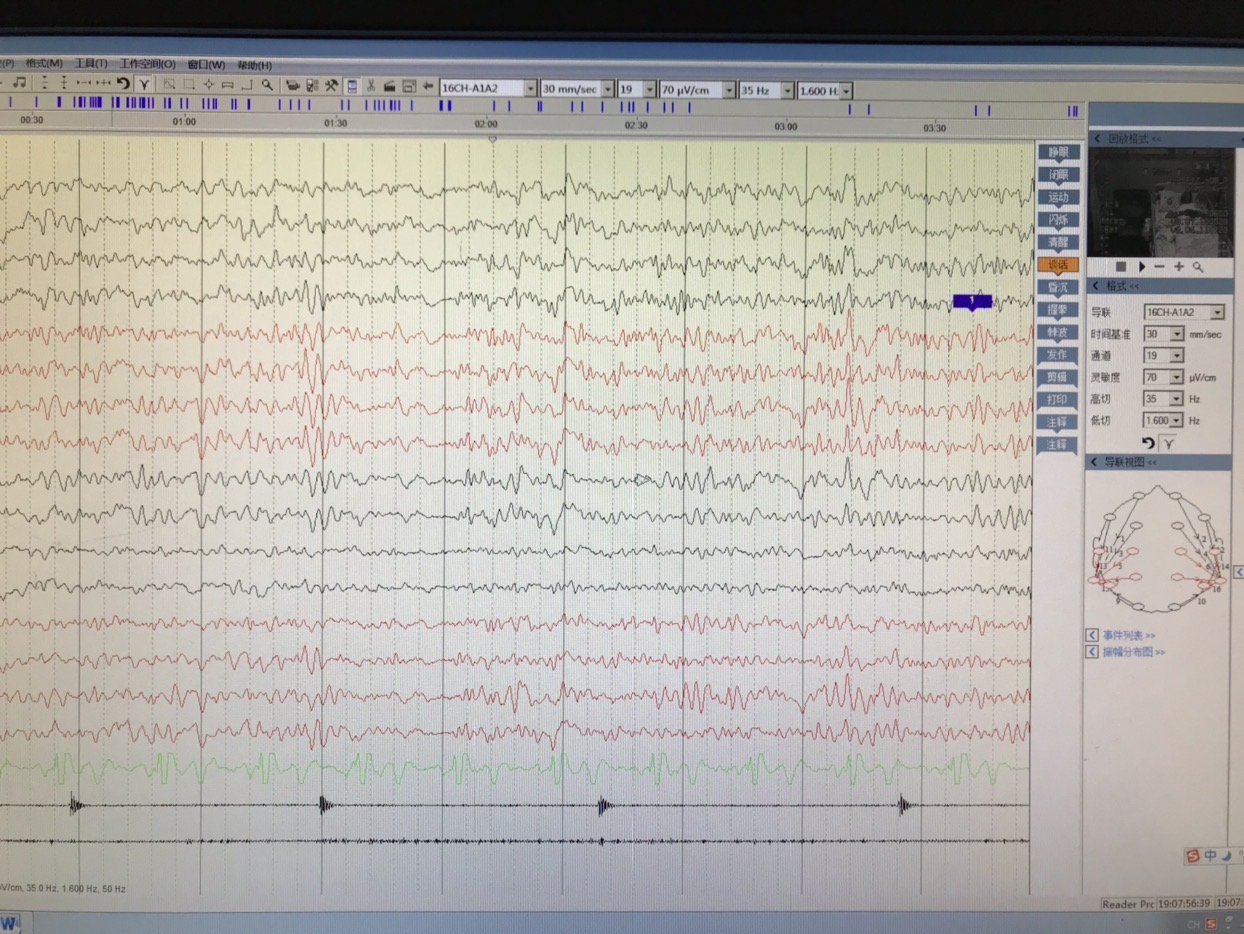

长程视频脑电监测提示左侧中央区、顶区、后颞区见中等量低-中-高波幅痫样放电。